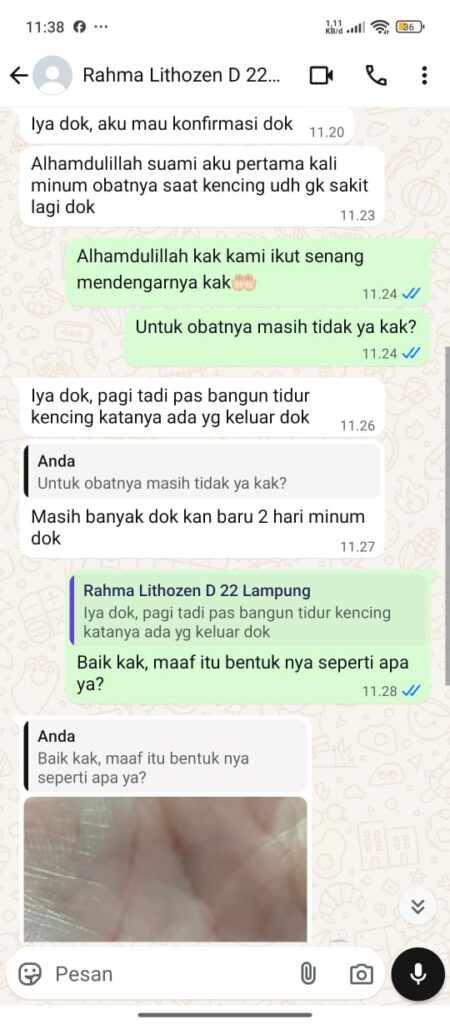

Ini Kata Mereka Yang Sudah Berhasil Sembuh dari Gangguan Ginjal

Dengan mengonsumsi obat gangguan ginjal Lithozen secara teratur dan berkonsultasi dengan CS Profesional kami, maka Anda akan mendapatkan hasil yang maksimal. Mayoritas konsumen Lithozen bisa sembuh total dalam pengobatan +/- 1 bulan